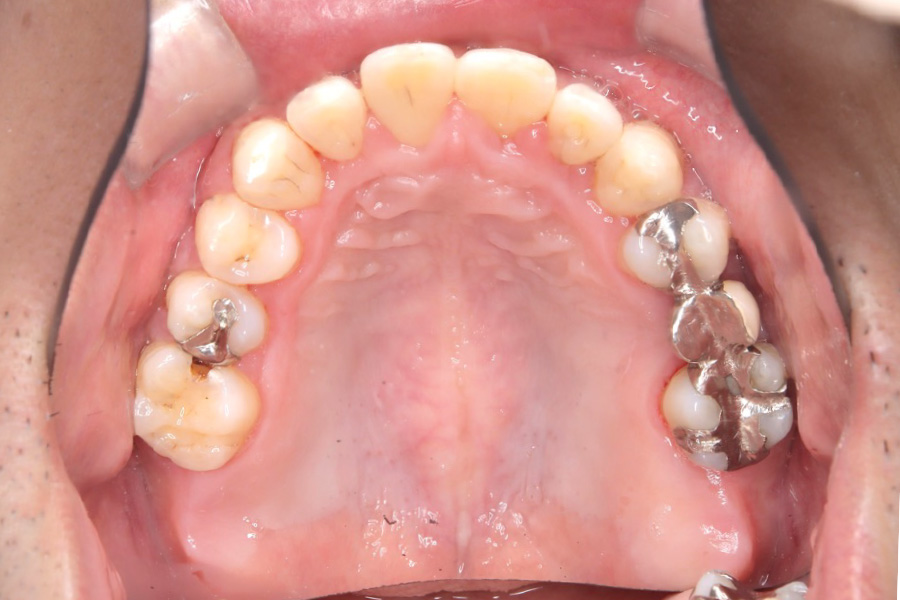

治療後

主訴 上の前歯を揃えたい

治療内容 インビザライン矯正

小臼歯抜歯

治療に伴うリスク 矯正終了後は、リテーナーを指示通りに使用し、歯の後戻りを防ぐ必要があります。